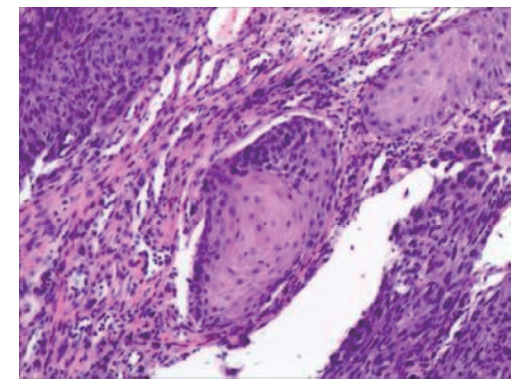

Shindo M, Yoshida Y, Tominaga K, et al. Skin metastasis of hypopharyngeal carcinoma to the nasal tip[J]. Yonago Acta Med, 2013, 56(2): 57-58.

Lopes Alexandre P, Matos R, Marques A, et al. Clown nose: a rare hypopharyngeal cancer metastasis[J]. Ear Nose Throat J, 2022: 1455613211069349. DOI: 10.1177/01455613211069349.

Kocak Z, Uygun K, Uzal MC, et al. Unusual metastatic site in a case of carcinoma of the hypopharynx: nasal tip[J]. J Otolaryngol, 2005, 34(4): 250-252. DOI: 10.2310/7070.2005.34409.